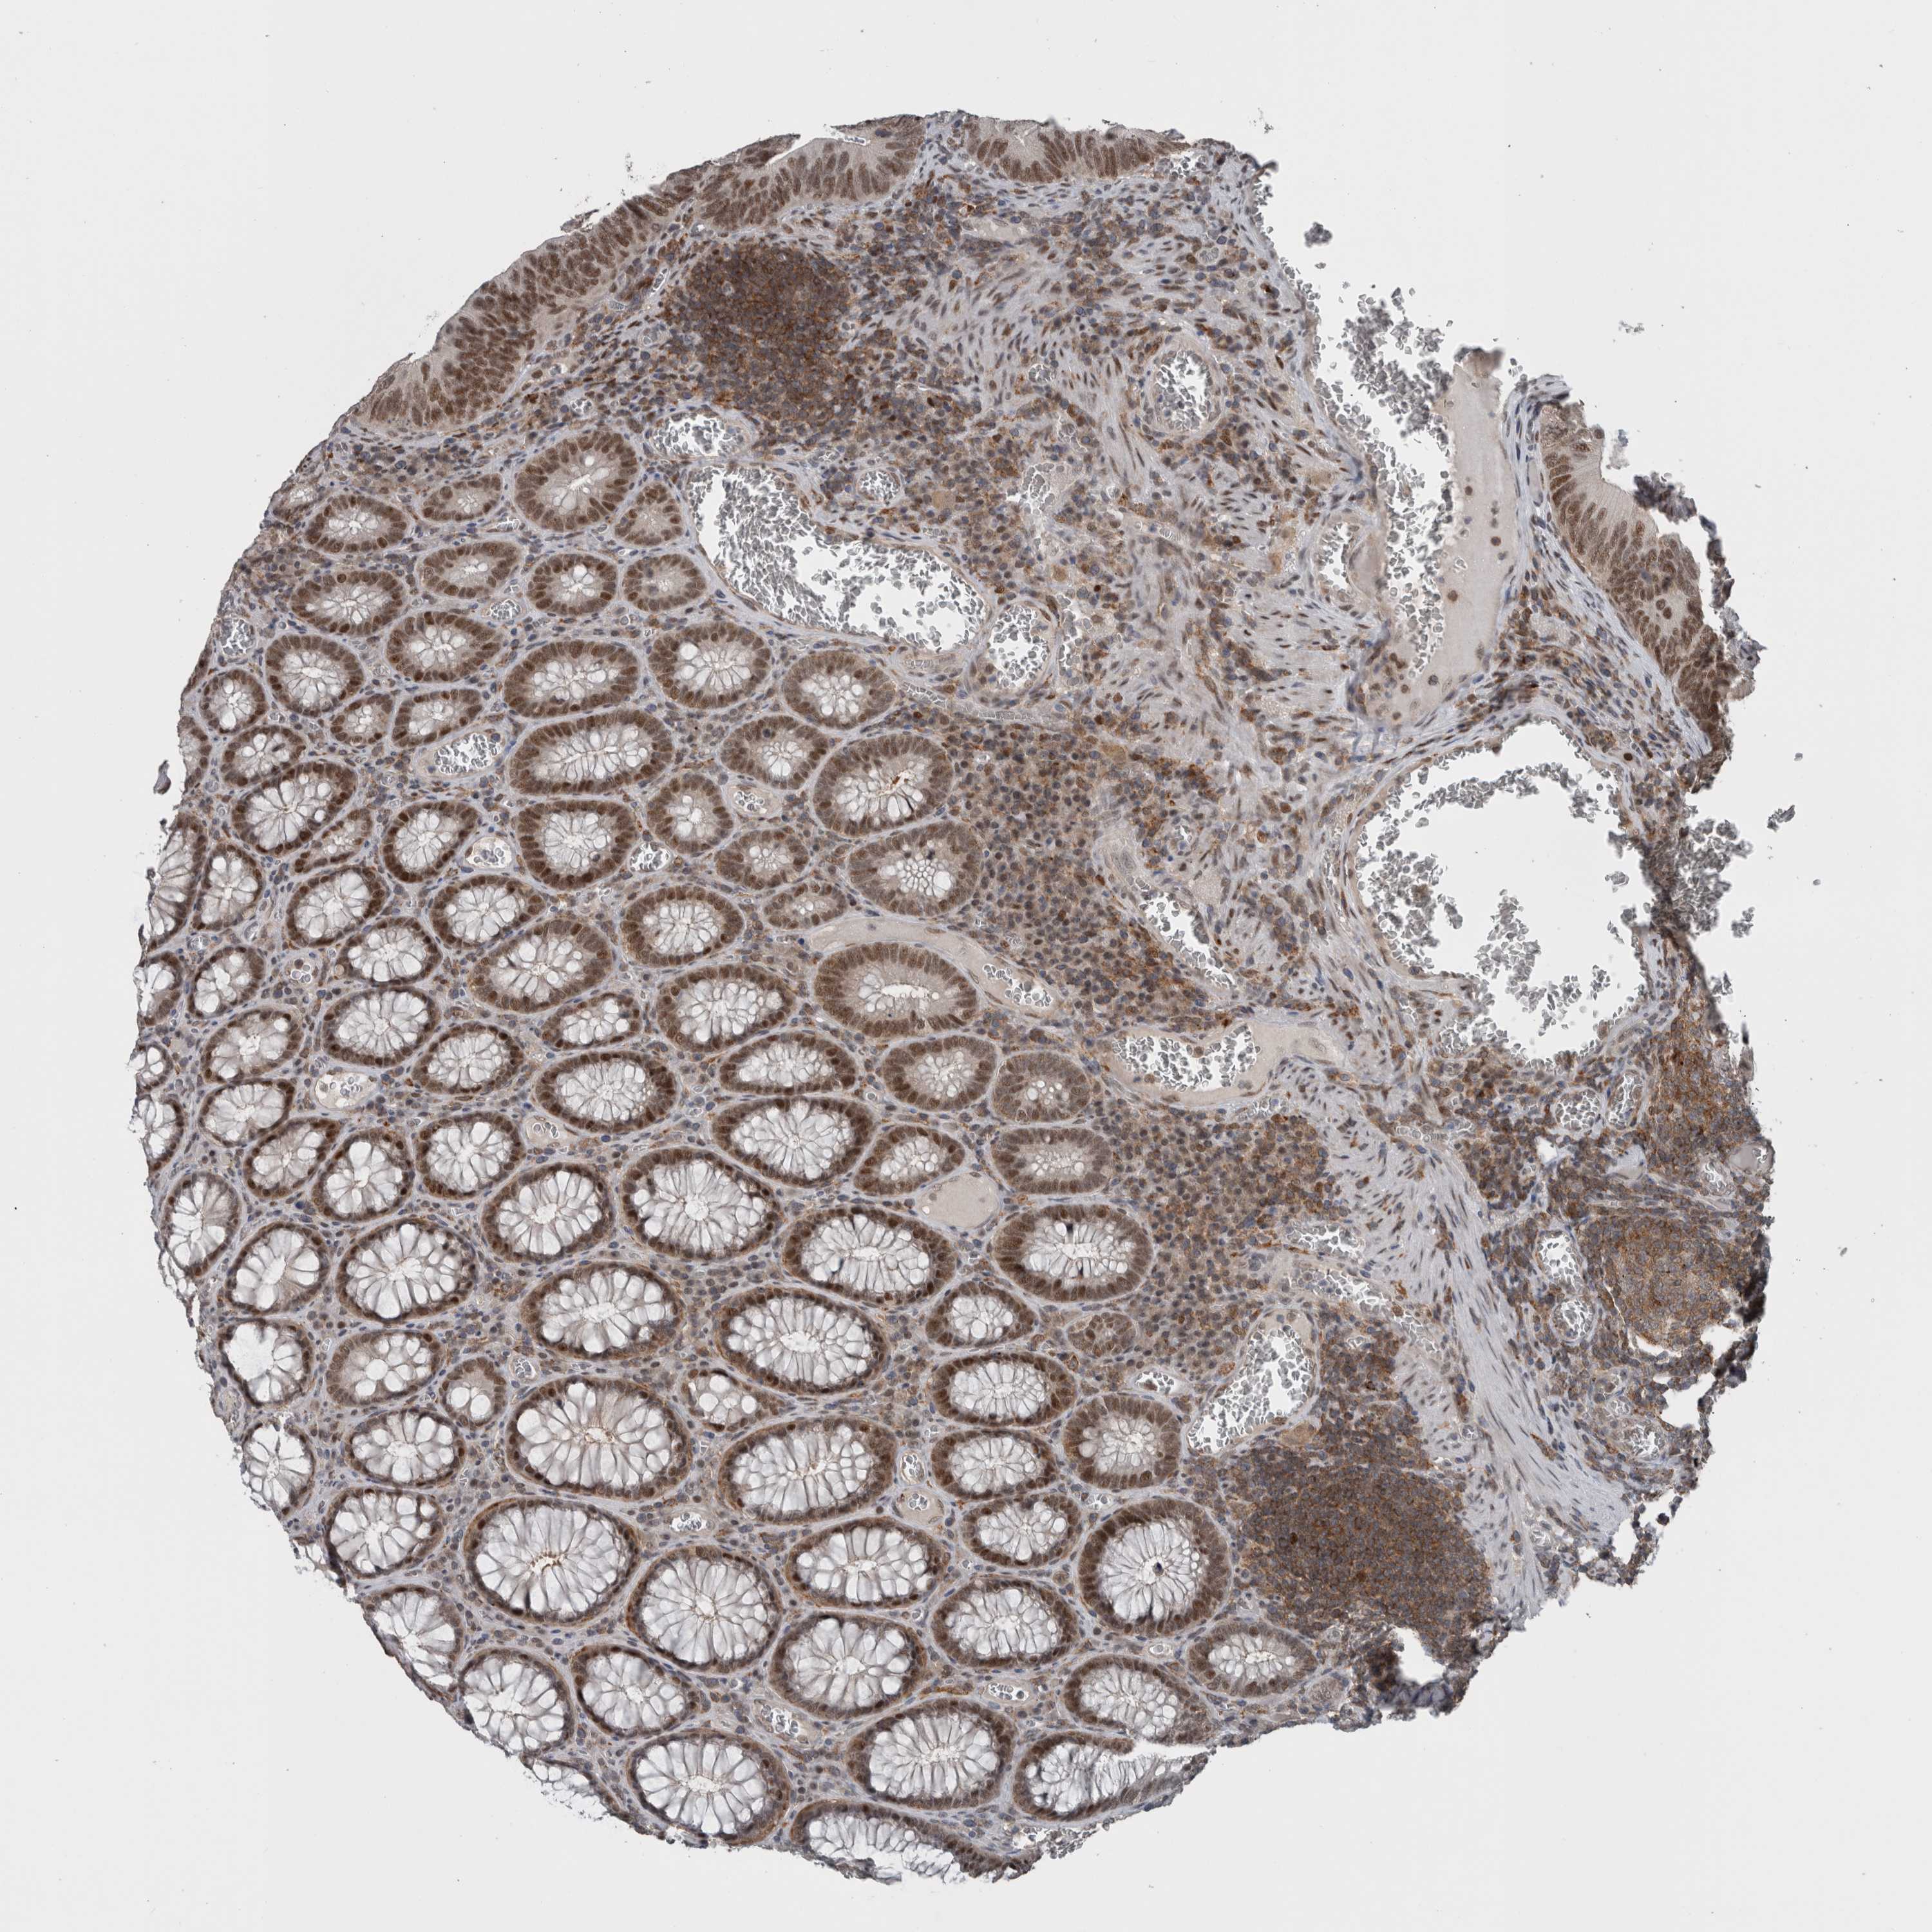

CANCER COLORECTAL CANCER Show tissue menu

Colorectal cancer

Human cancer

Colon adenocarcinoma